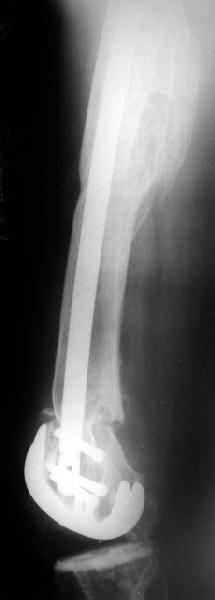

В итоге сделали антеградный остеосинтез. В дистракторе свежий перелом вправился сразу, а вот старый - оставил проблему, дистальный отлмомк остался все равно кзади. И гвоздь бы прошел кпереди от него, а ретроградный - перфорировал бы передний кортекс. Так что пришлось еще сделать чрескожную остеотомию через перелом, чтобы малость мобилизовать дистальный отломок. Снимки в прилжении.

Критика, комментарии, мнения?

The radiographs look excellent and a good outcome would be anticipated. The idea to osteotomize the femur shaft to compensate for the prior shaft malunion was clever and should work fine.

I can't actually see the osteotomy on either radiograph. Is it more proximal than we see in these radiographs or so well aligned as to be not visible?

The osteotomy was perfromed trough the fracture site. See the image.